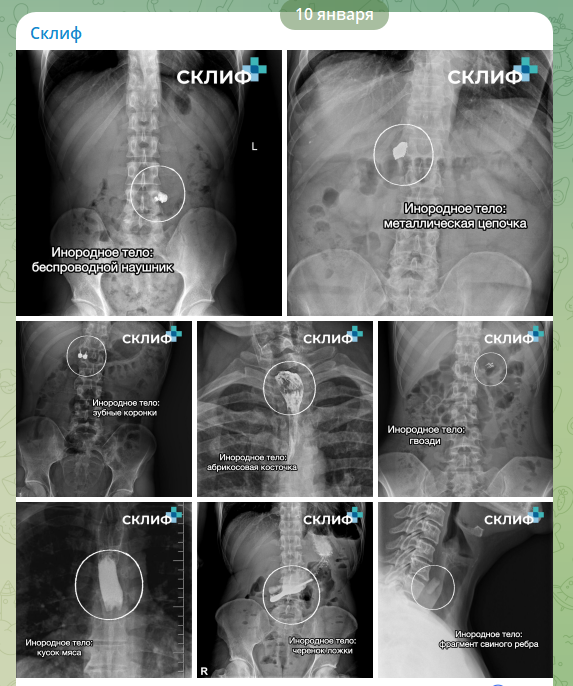

В "Склифе" показали на рентгене самые неожиданные находки в телах пациентов

Врачи московского НИИ скорой помощи имени Склифосовского рассказали о самых необычных предметах, которые пришлось извлекать из пациентов в прошедшем году. Публикация с соответствующими рентгеновскими снимками появилась 10 января в официальном Telegram-канале медучреждения.

Согласно сообщению пресс-службы института, в числе находок 2025 года оказались беспроводные наушники, ювелирные украшения, зубные коронки и даже строительные гвозди. Последние, как отметили медики, пациенты нередко зажимали в зубах во время ремонта и случайно проглатывали. Помимо этого, в списке упоминаются абрикосовая косточка, черенок от ложки и фрагмент свиного ребра.